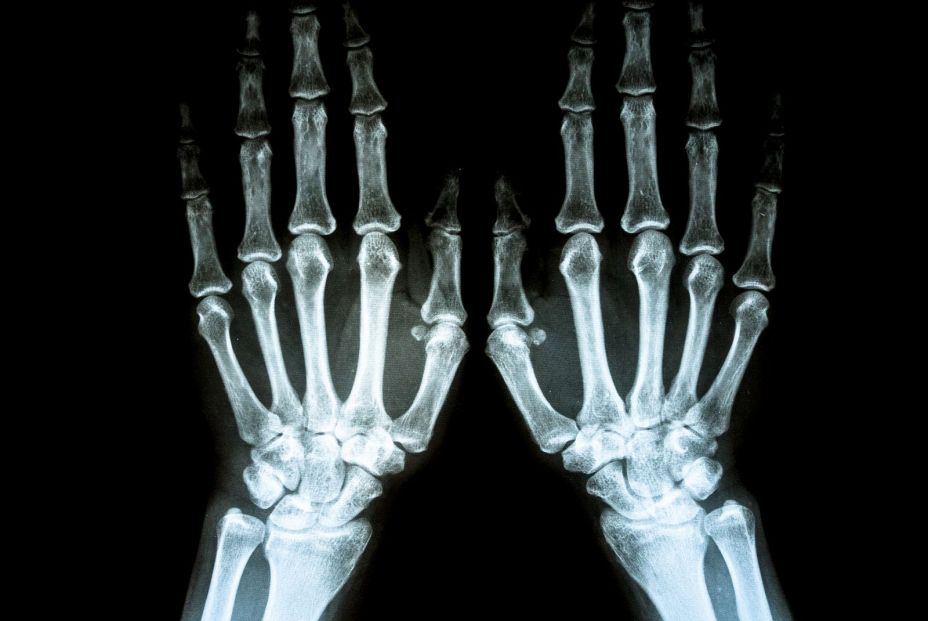

En la mano se encuentran diferentes huesos —metacarpianos y 3 falanges en cada uno de los dedos (excepto el pulgar que tiene 2)—que se unen entre ellos mediante articulaciones —etacarpofalángicas e interfalángicas—.

A su vez, la movilidad de nuestras manos depende de los tendones de diferentes músculos localizados en el antebrazo. Además, dentro de la mano existen también pequeños músculos cuya inervación, así como la sensibilidad de la mano, se debe a los nervios mediano, radial y cubital.

La artrosis es la degeneración de las articulaciones como consecuencia del sobreuso o del proceso de envejecimiento. No suele aparecer antes de los 40 años. Característicamente el dolor aparece con el uso y movimiento de la mano y calma en reposo. Si la artrosis es muy grave puede llegar a doler con mínima actividad o incluso en reposo o por las noches. Puede asociarse a la deformación de las articulaciones de la mano. Su diagnóstico se realiza mediante una radiografía.